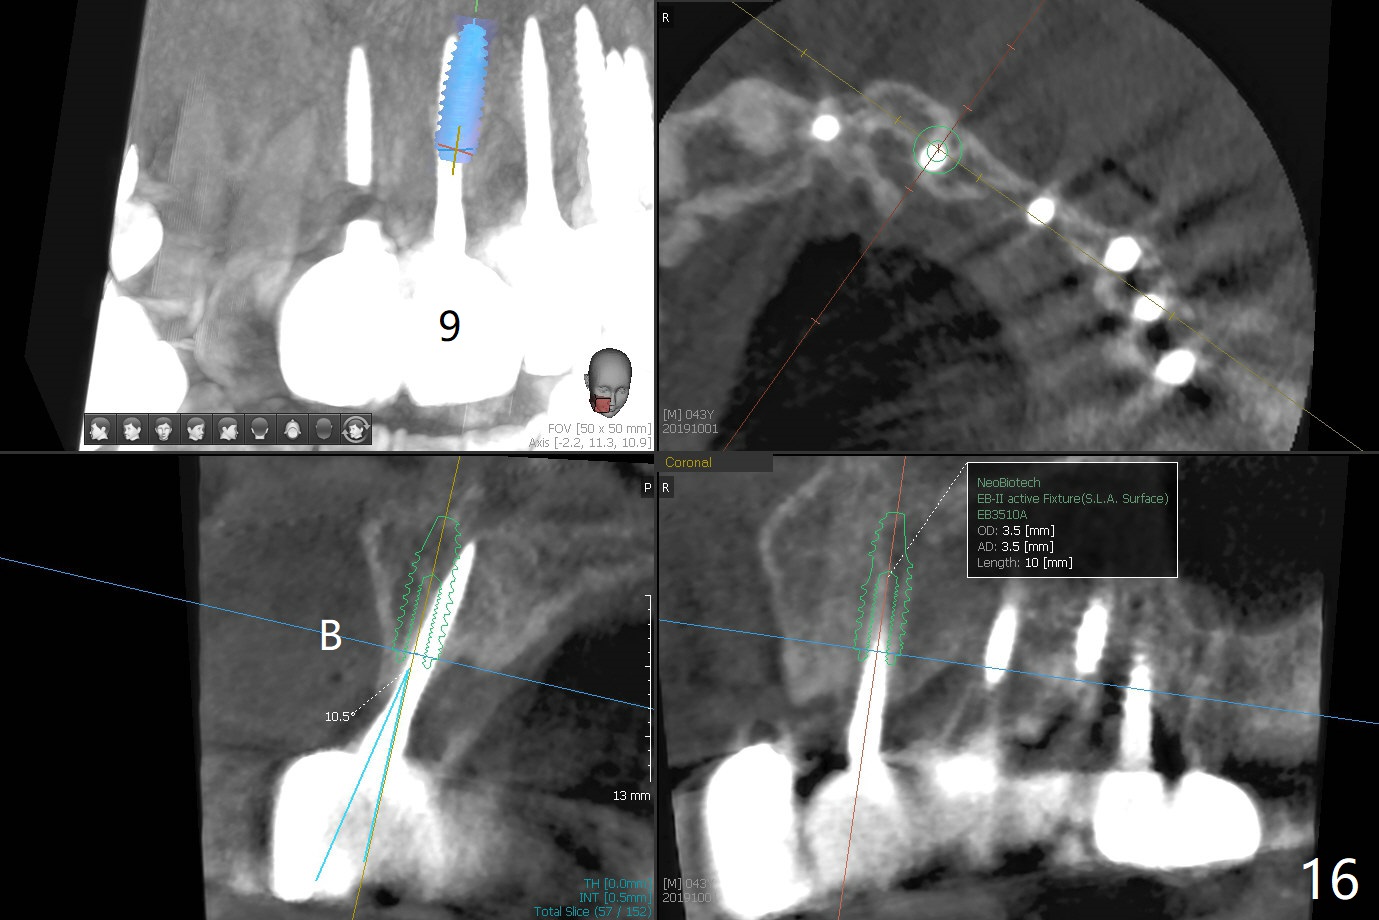

The ridge is wide enough for a 3.5x10 mm

implant (Fig.16 (CT taken when #8 implant fractured)). Return to Upper Incisor Immediate Implant, Trajectory II 1-Piece Prevent Fracture Xin Wei, DDS, PhD, MS 1st edition 10/01/2019, last revision 06/12/2020 |

A 43-year-old man has 6 of 1-piece implants in the maxilla (#8-13). His daughter's head hits his upper anterior teeth 7 months post cementation. Exam shows that the tooth #7 has mild percussion. Nine months later the implant crown at #8 becomes displaced and loose when he bites apple (Fig.1 arrow). Forceps are used to remove the crown, leaving a concave implant site (Fig.2). After the crown is bonded to the neighboring tooth/implant crown (Fig.3 *), the patient feels pain from the neighboring tooth. The alveolus is 4.3 mm wide (Fig.4 (2.9 mm preop)), allowing 2.5 or 3.0 mm immediate implant re-placement (Fig.5). A 2.0/3.0 mm trephine bur will be used for implant removal. Try to place the new implant slightly distal to improve the trajectory (Fig.6). Particulate and/or onlay graft is an option. Prepare dummy implants. As planned, the fractured implant is removed by using a 2.0/3.0 mm trephine bur following incision (Fig.7). After use of Lindamann bur to remove the distal bone, a 3x14(4) mm dummy implant is placed with 20 Ncm (Fig.8). A longer implant could be used (3x16(2 or 4) mm), but a 3.5x13 mm 1-piece implant is placed with ~ 50 Ncm after use 3.0 mm drill (Fig.9,10). Allograft is placed around the implant (Fig.9,10 *), followed by Amnion-Chorion membrane and 5-0 PGA sutures (Fig.11). Allograft placed around the implant (Fig.9 *) appears to be able to prevent implant thread exposure 4 months postop (Fig.12). PA is taken when the crown is cemented (Fig.13). Four months postop cementation of #8 crown, the patient returns because of #9 mobility (Fig.14). In fact the implant fractures when the loose crown is removed with forceps; there is bone loss at #10. Bone graft will be placed at #10 with sticky bone (PRFx1), while the implant at #9 is redo. The ridge is wide enough for a 3.5x10 mm implant (Fig.16 (CT taken when #8 implant fractured)). Also prepare Tatum angled 1-piece implant. The 2 mm implant is too thin when occlusion contact at #10-13 is incomplete. The crowns will be redone when the implant at #9 is osteointegrated.